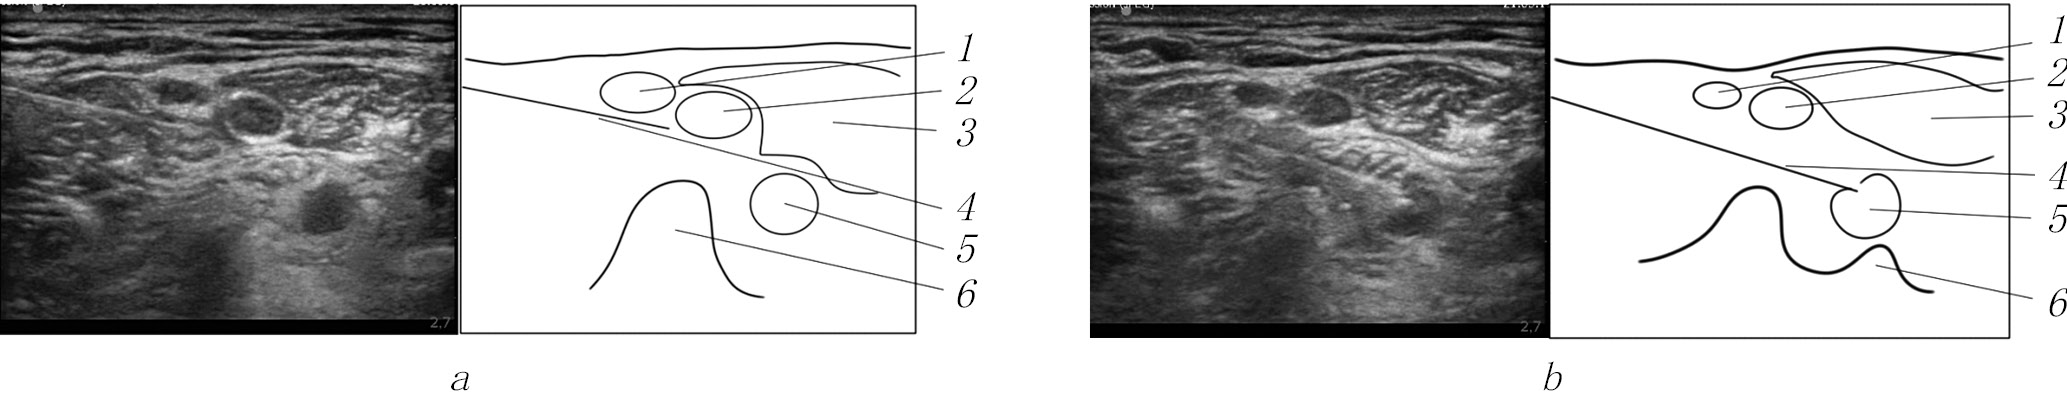

In Group 3, IBPB was performed under US navigation (Sonosite M-Turbo: 12 MHz linear sensor, transverse scanning at the level of the С6–С7 vertebrae with lateral access and long-axis imaging of the needle) and neurostimulation (Stimuplex HNS12, 0.5 mA, 1 Hz, 0.1 ms) with a selective block of the brachial plexus trunks. This was achieved by repeatedly repositioning the needle and introducing individual boluses of local anesthetic, not exceeding 0.5–1 mL, from each position. The solution was distributed around each trunk of the brachial plexus, which determined the necessary volume of local anesthetic. In total, 7–10 mL of 0.5% ropivacaine for block of the brachial plexus (Fig. 1) and 5–7 mL of 0.2% ropivacaine for the block of the superficial branches of the cervical plexus were used [15].

Fig. 1. Block of the upper, middle (a), and lower (b) trunks of the brachial plexus with lateral access: 1, the upper trunk of the brachial plexus; 2, the middle trunk of the brachial plexus; 3, the anterior scalene muscle; 4, needle; 5, the lower trunk of the brachial plexus; 6, the C7 vertebra